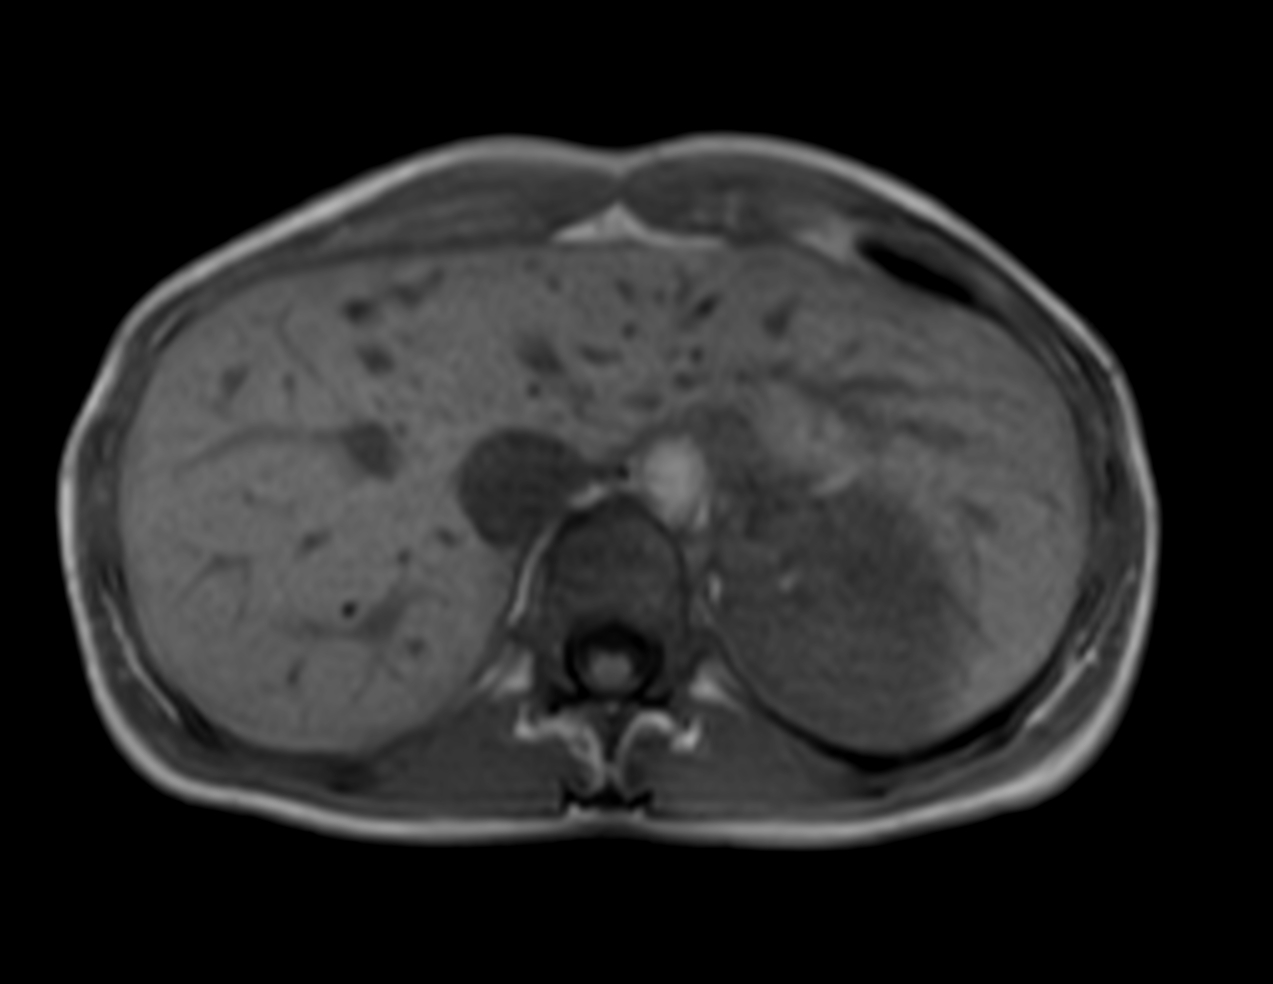

Axial mDIXON XD - T1w FFE (In Phase)